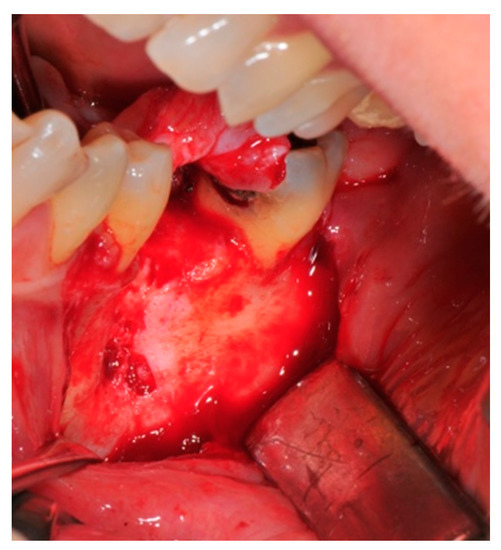

- Preparation of the receiving site: The exposed bone is cleaned from all of the remaining soft tissue and it is then prepared with multiple perforations using a small ball bur; this procedure is known as “bone refreshing” and it is performed to expose the cancellous portion of the residual bone, which shows a great osteo-genetic potential (Figure 6).